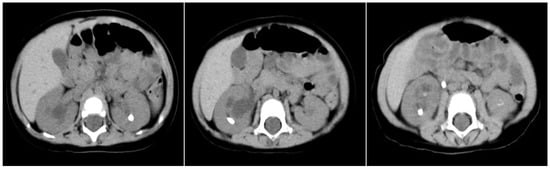

Background: Congenital disorders of glycosylation (CDG) are rare inborn errors of metabolism with multisystemic manifestations. SSR4-CDG is an ultra-rare X-linked subtype caused by pathogenic variants in SSR4, a component of the translocon-associated protein (TRAP) complex essential for protein translocation and N-glycosylation.

[...] Read more.

Background: Congenital disorders of glycosylation (CDG) are rare inborn errors of metabolism with multisystemic manifestations. SSR4-CDG is an ultra-rare X-linked subtype caused by pathogenic variants in SSR4, a component of the translocon-associated protein (TRAP) complex essential for protein translocation and N-glycosylation. Case presentation: We report a two-year-old Malaysian male presenting with global developmental delay, central hypotonia, microcephaly with complete agenesis of the corpus callosum, recurrent infections, bilateral vesicoureteral reflux, and failure to thrive. Growth parameters (weight, length, and head circumference) were persistently below the expected percentiles, indicating postnatal growth restriction. Initial metabolic and biochemical investigations for global developmental delay were unremarkable, apart from mild hyperammonemia. Transferrin isoform analysis demonstrated a type I CDG pattern, raising suspicion of a glycosylation defect. Results: Transferrin glycopeptide LC–MS/MS showed impaired N-glycan occupancy at both glycosylation sites (Asn432 and Asn630), with reduced fully sialylated glycoforms and increased non-glycosylated peptides. Targeted metabolomics using triple quadrupole LC–MS/MS revealed systemic abnormalities, including elevated arginine and phenylalanine, reduced glutamate, increased lysophosphatidylcholine (C24:0-LPC), and generalized depletion of free and acylcarnitines. Whole-exome sequencing identified a novel hemizygous SSR4 variant (c.98del; p.Pro33LeufsTer23) on the X chromosome, predicted to produce a truncated, nonfunctional protein. Conclusions: This is the first Malaysian patient with SSR4-CDG, comprehensively characterized using a multi-omics diagnostic workflow. The integration of glycoproteomics, metabolomics, and exome sequencing provided a detailed biochemical fingerprint that expands the clinical, genetic, and metabolic spectrum of SSR4-CDG and demonstrates the diagnostic and translational value of multi-omics approaches in inborn errors of metabolism.